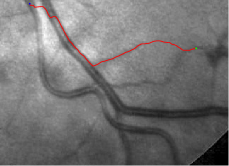

In this paper, we propose a coherence-penalized minimal path model, where the associated minimal paths favour to pass by a vessel that is located in the flatten region of an external feature map. We observe that along a piece of retinal vessel, the values of gray levels vary slowly. More specifically, retinal arteries have lower contrast of gray levels than veins due to the blood materials and imaging modality. In other words, in some extent the arteries and veins are distinguishable in terms of vesselness values. Such an observation can be used to solve the short branches problem that the minimal paths associated to a metric may pass through segments belonging to different vessels as shown in Figs. 1b and 1c. Fig. 1d shows the result from the proposed method, which can avoid such problem. Fig. 1a gives the artery-vein (AV) groundtruth. In this paper, we denote by blue and green dots the source and end points respectively.

Compare to existing minimal path models. The Riemannian metrics used in [1, 4, 5] are based on the local pointwise information. The curvature-penalized metric [7, 6] and the proposed coherence-penalized metric are able to consider more constraints, i.e., the rigidity for [7, 6] and feature coherence for our metric. These constraints are beneficial to the respective geodesics to reduce the risk of short branches combination problem. Compared to the curvature-penalized metric, our method can be more flexible since the feature map can be produced dependently on the task. In retinal imaging, veins and arteries are distinguishable in terms of gray levels or vesselness values, satisfying the formulation of the proposed model. Especially for vessels with strong tortuosity, the curvature-penalized metric, which favours a smooth curve, fails to catch the expected vessels as shown in the left column of Fig. 2. From the right column of Fig. 2, one can see that our model can obtain a good result.

Validation. We validate our minimal path model on respective 54 and 30 patches obtained from the DRIVE [14, 15] and the IOSTAR [16] datasets with AV groundtruth. Each artery involved in these parches locates near a vein or crossing it at least once. Our goal is to extract the artery between two given points. In order to get the quantitative evaluation, we first convert each continuous spatial path to an 4-connected digital path which is considered as a pixel collection. We denote by the collection of digital path pixels inside the artery groundtruth map . Thus, a measure can be simply defined as , where and mean the respective number of elements involved in and . We compare our model to four existing minimal path models: the isotropic Riemannian (IR) model [1], the anisotropic radius-lifted Riemannian (ArR) model [4], the isotropic orientation-lifted Riemannian (IoR) model [5] and the curvature-penalized (CuP) model [7]. The construction of these metrics are based on the OOF outputs [12]. Note that a centerline-based potential is chosen so that we remove the radius dimension of [5] to reduce computation complexity. The results in terms of the score are presented in Table 1, including the average (Avg.), maximum (Max.), minimum (Min.) and standard deviation (Std.) values. In both DRIVE and IOSTAR datasets, our method can achieve the best performances thanks to the coherence penalization. Note that in Table 1, we evaluate our method by using the refined paths instead of using the original coherence-penalized minimal paths. For comparisons in visualization, we show the minimal paths from the ArR metric , the CuP metric and the proposed coherence-penalized metric on three retinal patches as shown in Fig. 3. The targeted artery vessels which cross veins at least once are labeled by red color in column 1. The paths shown in column 4 from the proposed metric are results after refinement. One can claim that our method indeed can catch expected arteries while other metrics fall into the traps of short branches combination.